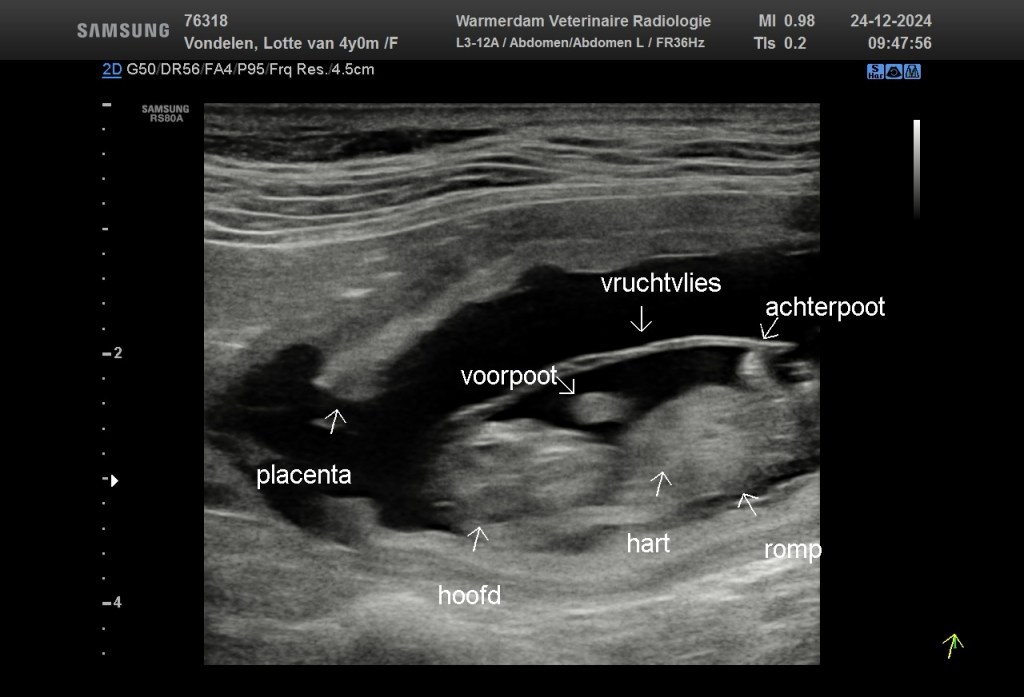

Our Christmas is as good as it can get as a gundog lover. Yesterday I managed to hunt a full Christmas dinner that I will prepare myself for the family in law. I will tell more about that later because we are totally consumed with happiness as the ultrasound this morning showed that Lotte (Flatastic Red Strength) is with pups. We expect a normal sized litter – thank God it will not be a as many as a football team. We are looking forward to a wonderful time and so thrilled to welcome the puppies at the end of January.